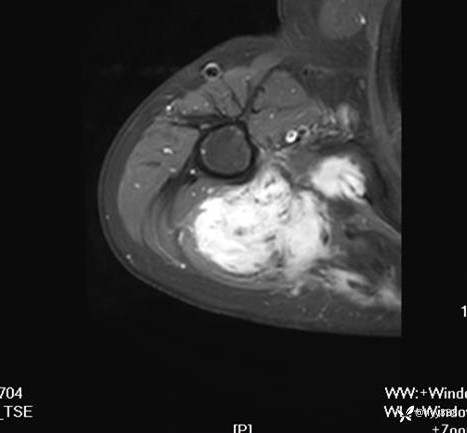

MRI AXI T1WI+T2WIfs

AXI T1WI+T2WIfs

CE